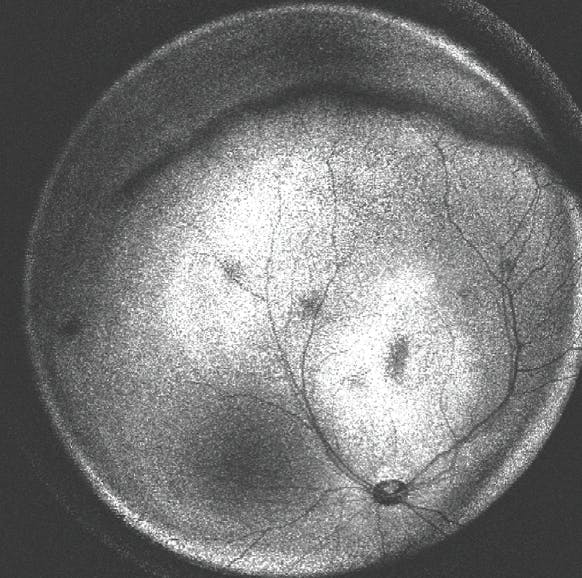

Ultra-widefield (UWF) OCT, still in the research setting for ROP, is offering new insights, including the understanding that stage exists along a spectrum (Figure 2).8 Specifically, UWF OCT can detect the thickness of the ridge and show that it correlates continuously with the clinical diagnosis of stage.8 Further, UWF OCT may be able to detect the progression of the stage earlier than a clinical examination or traditional fundus photography.8 Quantitative and objective biomarkers, such as ridge thickness, have the potential to eliminate the problems with interrater reliability.

<p>Figure 2. En face ultra-widefield OCT clearly demonstrates the ridge in a neonate with stage 2 ROP. Image courtesy of Yifan Jian, PhD, and Mani Woodward</p>

Figure 2. En face ultra-widefield OCT clearly demonstrates the ridge in a neonate with stage 2 ROP. Image courtesy of Yifan Jian, PhD, and Mani Woodward

This technology, if brought to market, could have tremendous utility in creating objective markers for staging disease, tracking progression earlier, and determining the incidence of neovascularization.